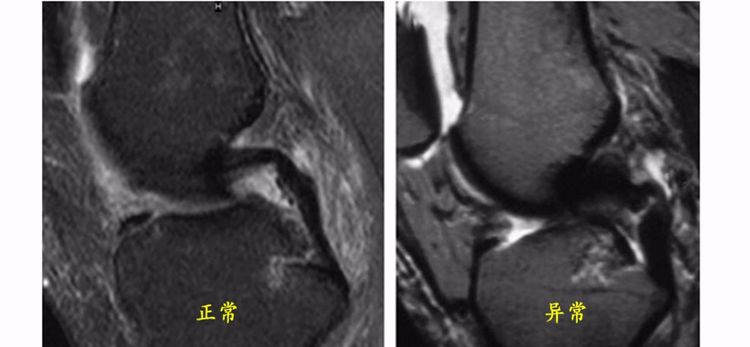

ACL的正常MRI表现——

1.各序列均为低信号。

2.韧带平直,边界清楚,有较好的张力。

3.韧带内可有脂肪及滑膜条纹影。